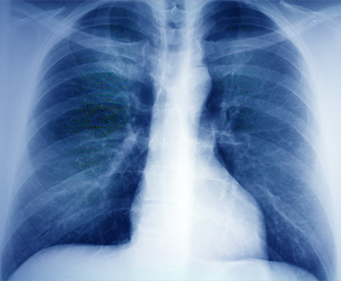

功能检查是测量个人的呼吸能力和评价肺功能是否正常的检查,

有助于判定患者诉说的症状(呼吸困难等)、

呼吸系统症状的严重程度,并设定治疗方向及评价治疗效果。

肺功能检查种类

肺功能检查种类 主要检查内容

肺活量检查 可检查肺活量是否优于正常标准,

还可检查呼吸道有无功能衰退。

肺容积检查 除患者的总肺容积以及平时的呼吸量、

余气量(用力呼气后生在肺部内的空气量)外,

还可正确测量呼吸道抵抗等各种指标,从而有效评价肺功能。